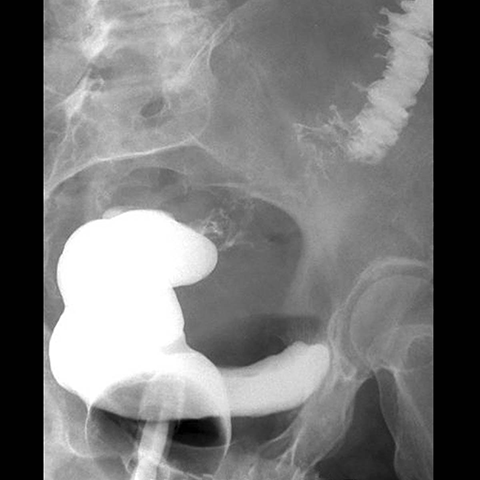

65 year-old male presents with fever and LLQ pain. [1 of 5]